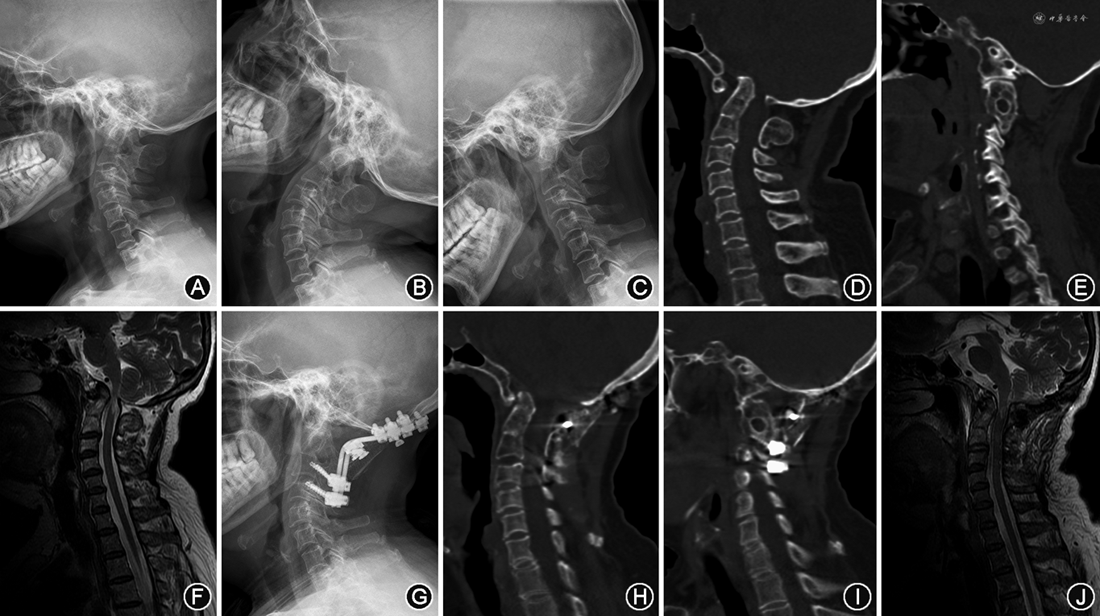

患者女,62岁,因颈部疼痛2年,加重伴肢体麻木乏力6个月入院,诊断为:(1)颅底凹陷畸形伴AAD;(2)寰枕融合;(3)C2、C3椎体融合。术前JOA评分10分,ADI:5 mm,ML:4 mm,WL:2 mm,CMA:132°。行TSDR枕颈融合术,术后症状缓解,末次随访时JOA评分为15分,ADI:1 mm,ML:0 mm,WL:-1 mm,CMA:141°(图3)。